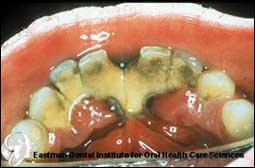

أمراض اللثة والأنسجة الداعمة Periodontal Disease

التدخين من أهم أسباب الإصابة بأمراض اللثة!!

هل تعاني من نزف في اللثة وحساسية في الأسنان؟ هل تشعر بتخلخل في أسنانك وظهور فراغات ما بين أسنانك؟ هل تتضايق من رائحة فم مزعجة ومن طعم سيئ؟ هل لاحظت ان.........